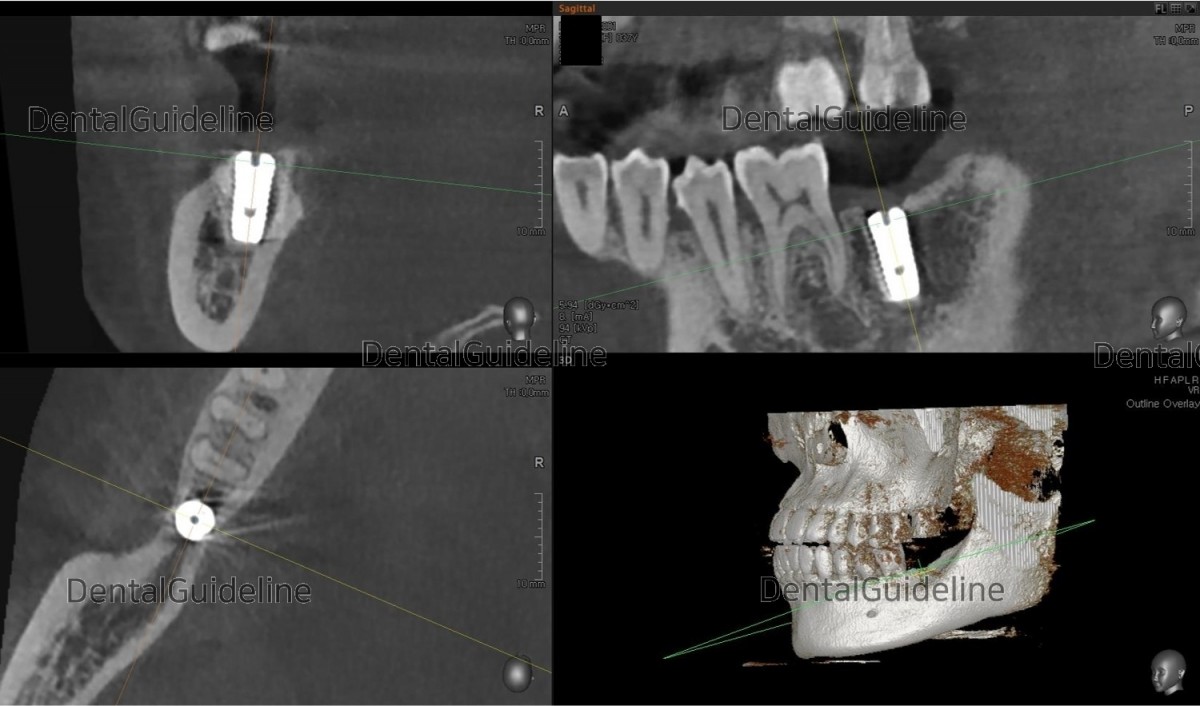

3. CBCT scan and simple surgical simulation.

8. CBCT scan view